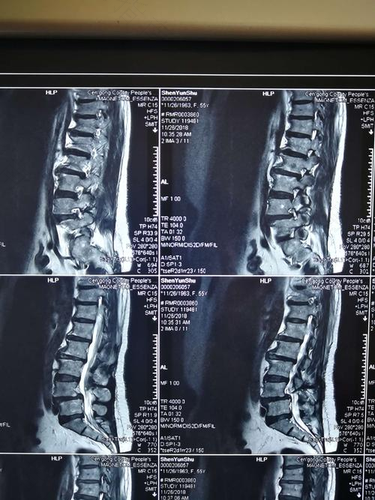

患者也可以采取针灸疗法,能治疗面瘫,腰脱,减肥,肩周炎,颈椎病,头痛,三叉神经痛以及带状疱疹等疾病。患者可以去医院咨询医生,在医生的指导下再进行治疗,不可以自己随便服用药物。